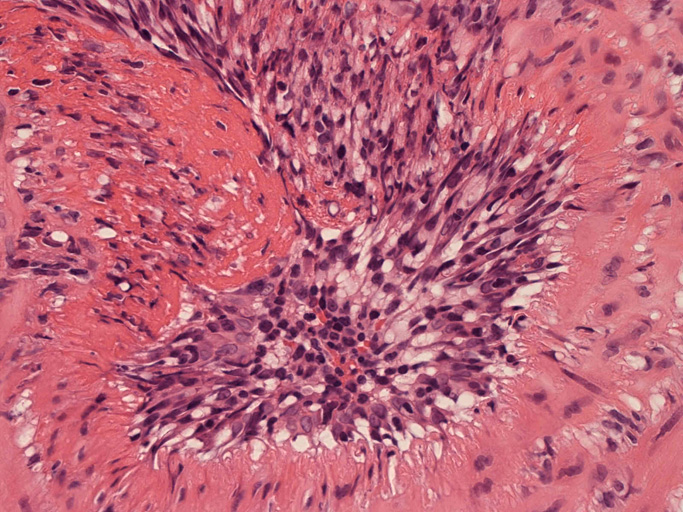

皮膚の血管(静脈・細動脈)病変、脂肪織炎 (サムネイルをクリックすると大きな画像が見られます)

fibrinoid necrosis

fibrinoid necrosis(拡大)

免疫染色:血管腔を閉塞する細胞の多くはCD68, CD163陽性細胞. CD34陽性内皮が保たれている。